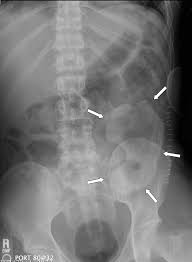

تجويف البطن هو مساحة كبيرة تقع بين الصدر والحوض ويحتوي على عدد من الأعضاء مثل الكبد والمعدة والبنكرياس. يتمتع بدرجة حرارة طبيعية للجسم ولن يتعرف على عظام الجمجمة أو الأيدي المصابة على أنها غريبة وسيوفر إمدادات الدم والمواد المغذية للأعضاء المزروعة المصابة.